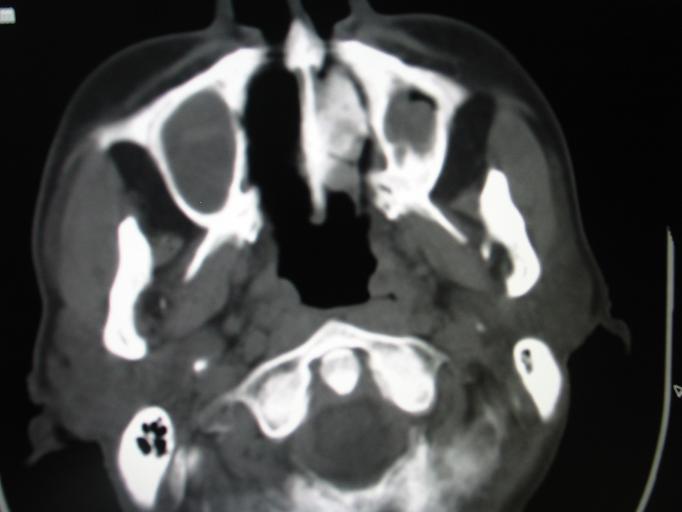

CT50267:男.61岁。鼻塞.

男.61岁。鼻塞,有时鼻滴带血

1、多考虑内翻性乳头状瘤,鼻息肉待除外。

2、双侧筛窦炎、上颌窦炎。zhichi

1)双侧鼻腔及双侧上颌窦息肉。2)双侧上颌窦、双侧筛窦及双侧蝶窦炎。

副鼻窦炎;鼻腔息肉样变,不除外鼻咽癌。